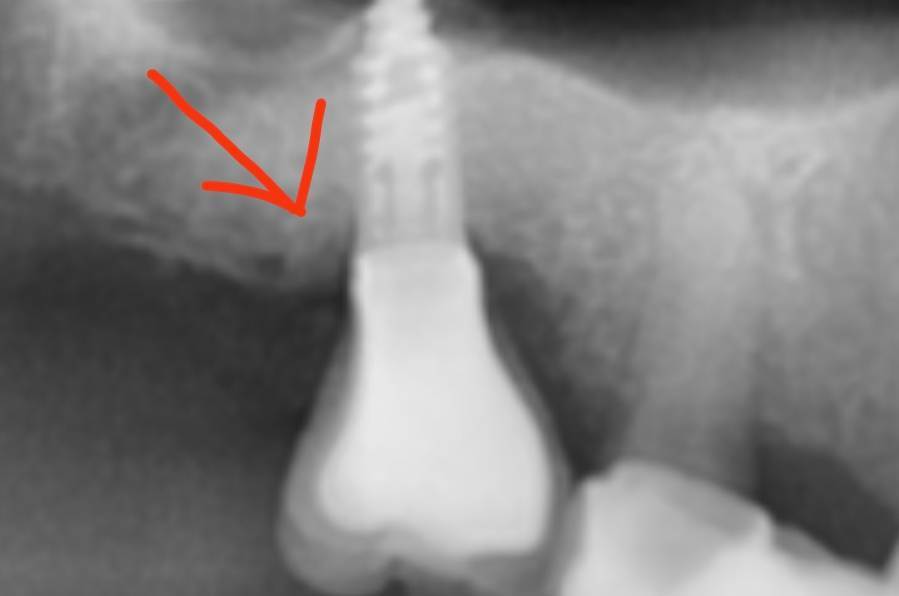

Irouil Опубликовано 8 августа, 2023 Автор Поделиться Опубликовано 8 августа, 2023 Ссылка на комментарий

АнтонТЛТ Опубликовано 8 августа, 2023 Поделиться Опубликовано 8 августа, 2023 Лучше прицельные снимки делать, на таких не рассмотреть ничего. Форум сильно сжимает изображение. Либо кадрировать эти снимки. Почему тибейсы такие короткие используются? Ссылка на комментарий

NazranDantist Опубликовано 8 августа, 2023 Поделиться Опубликовано 8 августа, 2023 (изменено) Вполне возможно упирается в ткани протетика, закручивали с усилием. Только ортопед вам правду расскажет). Если пассивно закручивал протетику, то откручивается по не зависящим от нас причинам, в противном случае- винт под напряжением, либо в тканях упирается, либо контактный пункт. Изменено 8 августа, 2023 пользователем NazranDantist 1 Ссылка на комментарий

Irouil Опубликовано 9 августа, 2023 Автор Поделиться Опубликовано 9 августа, 2023 @АнтонТЛТ думаете короткие ти бейсы могут повлиять? Я сейчас не про пассивность. Лаба работает вообще с большим количеством нареканий, самое смешное в этом то, что она наша)) @NazranDantist согласен, есть риски, что какие-то сели внатяг. Ссылка на комментарий